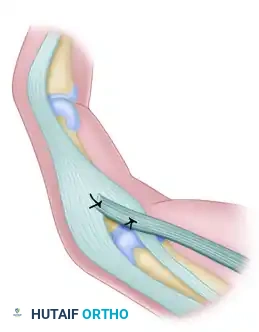

* Oberlin Transfer: Transfer of expendable motor fascicles from the ulnar nerve (usually supplying the FCU) directly to the biceps motor branch of the musculocutaneous nerve.